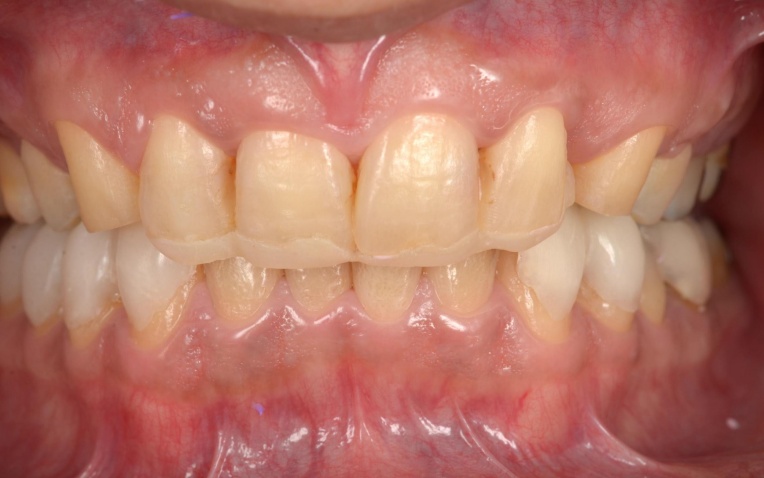

治療後

顎の位置が改善し、噛み合わせが安定したことを確認したあと、装着していた仮歯を除去してセラミックの被せ物に置き換えました。

最後に噛み合わせや見た目に問題がないかをしっかりとチェックして、治療を終了しています。

丈夫で審美性の高い「セラミック」で、奥歯を治療します。

メリット:自然な見た目になる。長期的に噛み合わせが安定しやすくなる